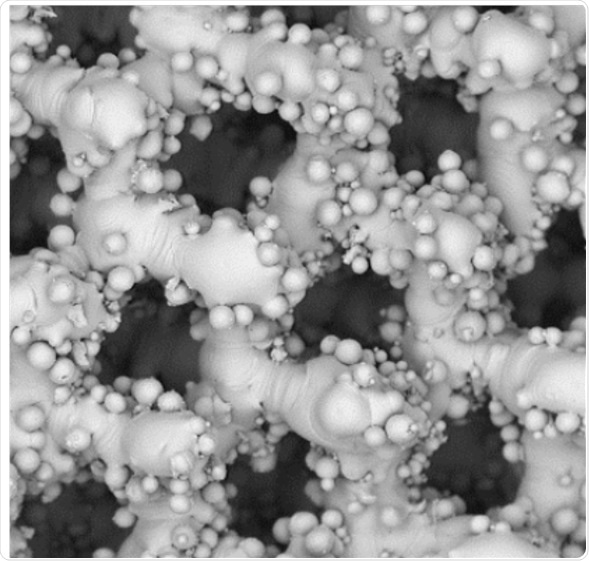

In another study on skeletal injuries and tissue engineering conducted in Poland, the application of titanium scaffolds in tissue engineering2 was evaluated. It is possible to replace bone loss using tailored titanium scaffolds, which are supporting net shaped structures, created by additive manufacturing. It is essential to remove these additives during a chemical treatment used for polishing the scaffolds.

The effect of this chemical polishing on the porosity and morphology of the scaffolds was studied using a SEM. The size of the chemical particles was determined using the ParticleMetric software and the morphology before and after polishing was shown by the subsequent SEM imaging. The study was successfully completed using the PoroMetric software using which the effect of chemical polishing on the scaffold’s pores was visualized and measured by the researchers.

SEM images of scaffoldSEM images of scaffold

Figure 2. SEM images of scaffold. Adapted from 1.